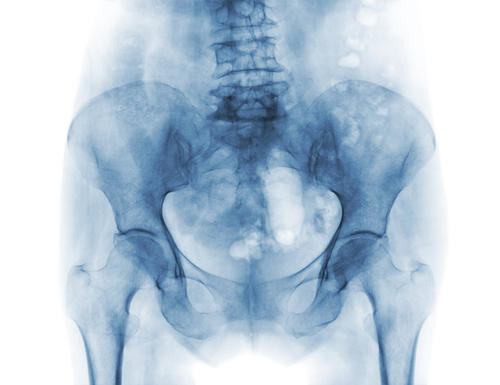

Фотогалерея

Рентген-аппарат